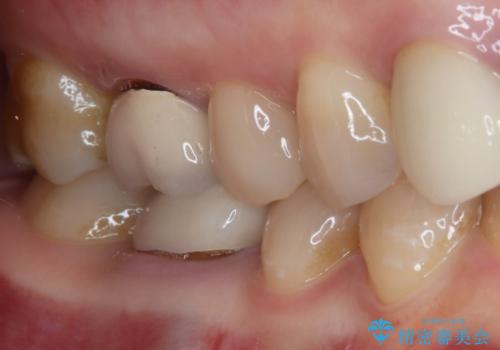

残念ながら歯冠から歯根に向かって破折が認められたため、患者様了解のもと、抜歯してインプラントの即時埋入を行いました。

インプラントと骨の安定程度を測定したところ、十分な数値が得られたため、速やかに仮歯を装着して咬合回復をさせることができました。

抜歯を含めた外科処置を1回に抑えることができ、あっという間に治療を終えることができました。